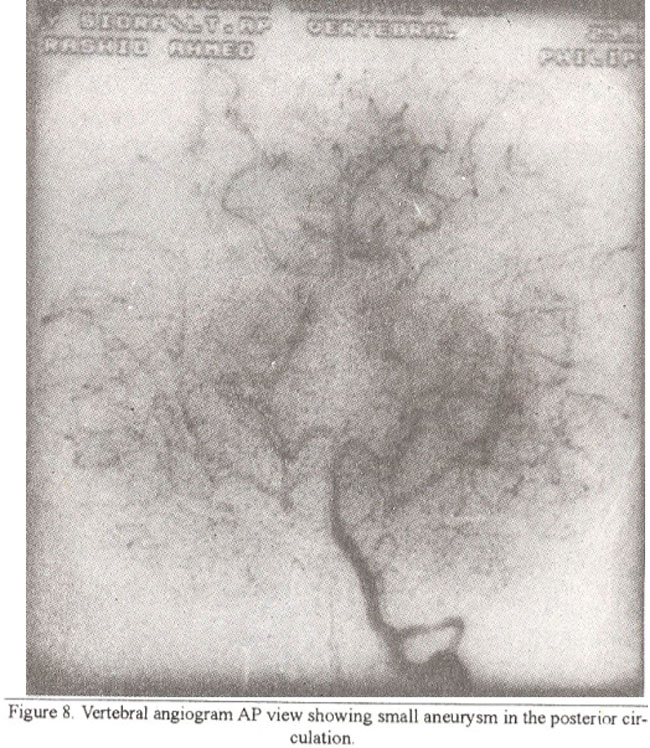

Involvement of vertebral artery was seen in three cases, while it was spared in one case. Small aneurysms were seen within the posterior circulation and collateral vessels in two cases (Figure 8).